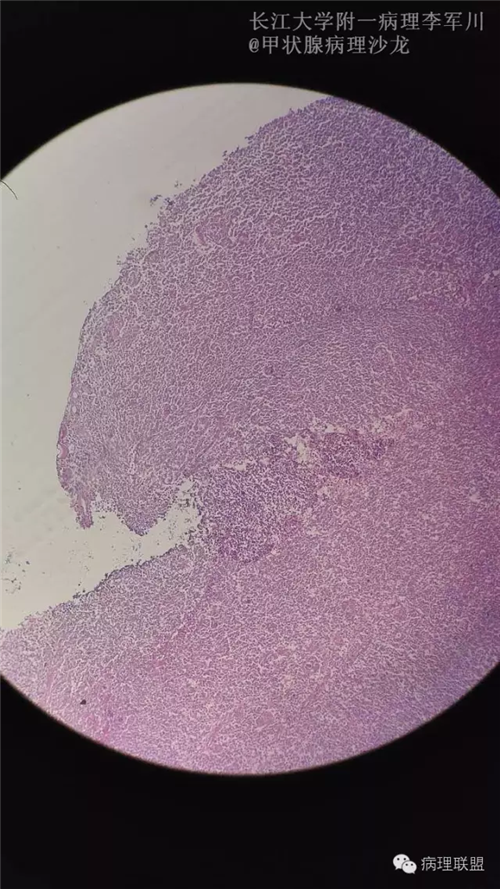

甲状腺病变中的MALT?

女,40余岁,右侧甲状腺肿块,直径约3cm。